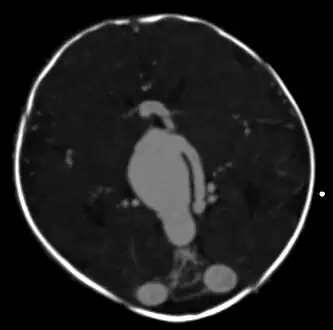

![]() | |

| Large arteriovenous malformation of the parietal lobe | |

An AVM diagnosis is established by neuroimaging studies after a complete neurological and physical examination.[5][11] Three main techniques are used to visualize the brain and search for AVM: computed tomography (CT), magnetic resonance imaging (MRI), and cerebral angiography.[11] A CT scan of the head is usually performed first when the subject is symptomatic. It can suggest the approximate site of the bleed.[3] MRI is more sensitive than CT in the diagnosis of AVMs and provides better information about the exact location of the malformation.[11] More detailed pictures of the tangle of blood vessels that compose an AVM can be obtained by using radioactive agents injected into the blood stream. If a CT is used in conjunctiangiogram, this is called a computerized tomography angiogram; while, if MRI is used it is called magnetic resonance angiogram.[3][11] The best images of an AVM are obtained through cerebral angiography. This procedure involves using a catheter, threaded through an artery up to the head, to deliver a contrast agent into the AVM. As the contrast agent flows through the AVM structure, a sequence of X-ray images are obtained.[11]